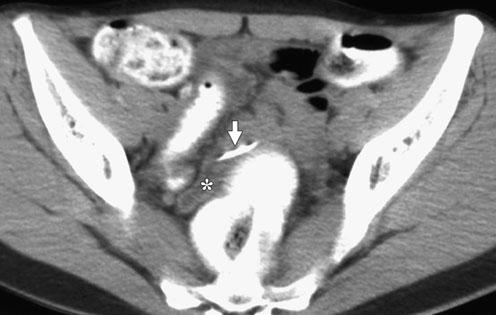

Hình 28: Thủng túi thừa Meckel ở bệnh nhân nữ 33 tuổi. A, CT uống và tiêm cản quang, thấy khí dò ra từ túi thừa Meckel ở ¼ bụng dưới phải (hoa thị). Hồi tràng và mỡ mạc treo thâm nhiễm bao xung quanh ( mũi tên). B, Coronal tái tạo: túi thừa Meckel bị dò (dấu hoa thị) và dày thành hồi tràng. (Alexandra Platon , Pascal Gervaz (2010). Computed tomography of complicated Meckel’s diverticulum in adults. Insights Imaging 1:56).